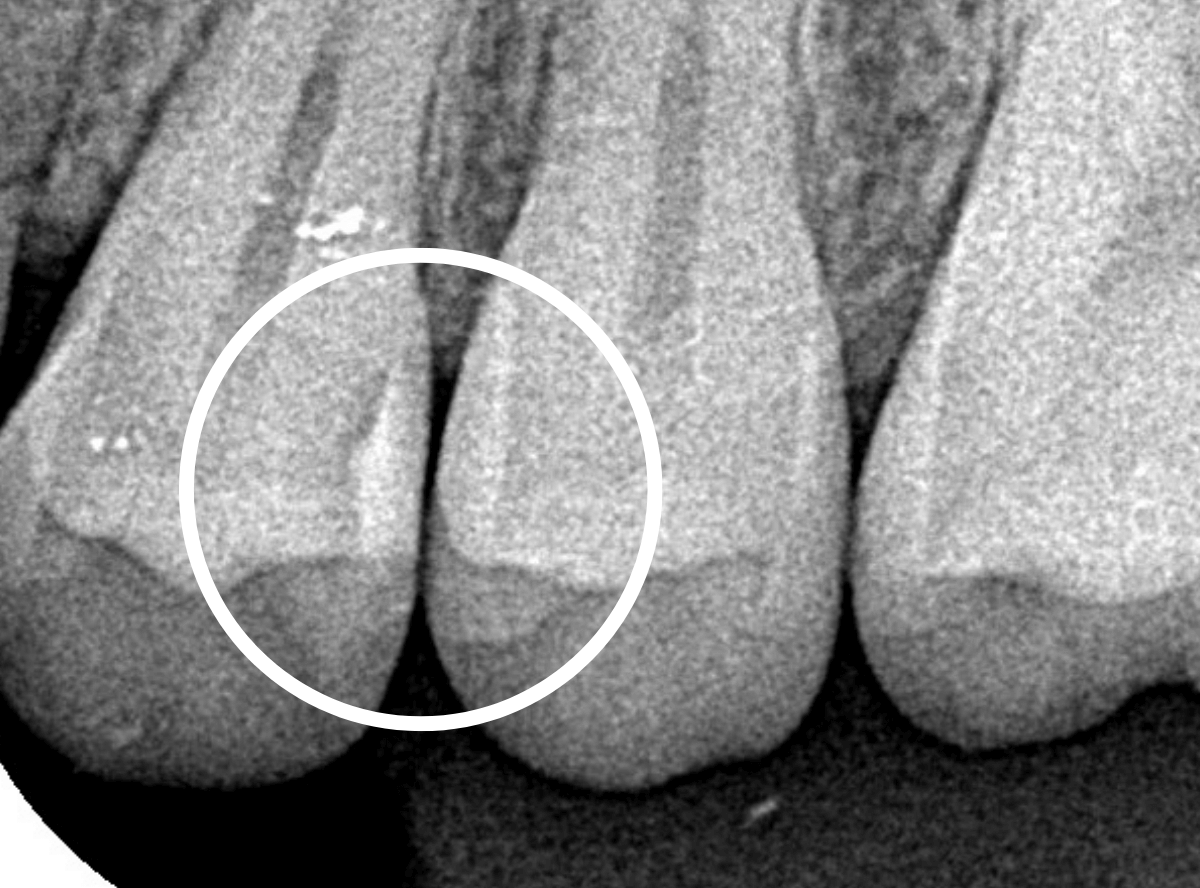

レントゲン写真を撮影してみました。

以前に小さな虫歯の治療をして、その中が虫歯になっているようです。

経過観察にする先生もいそうな、微妙な映り方です。